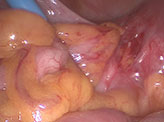

At laparoscopy, the bowel was seen densely adherent to both adnexa, making it difficult to visualize the adnexa. Bowel (rectosigmoid) was adherent to the posterior surface as well as fundus of the uterus.

Left adnexa completely covered with dense bowel adhesions